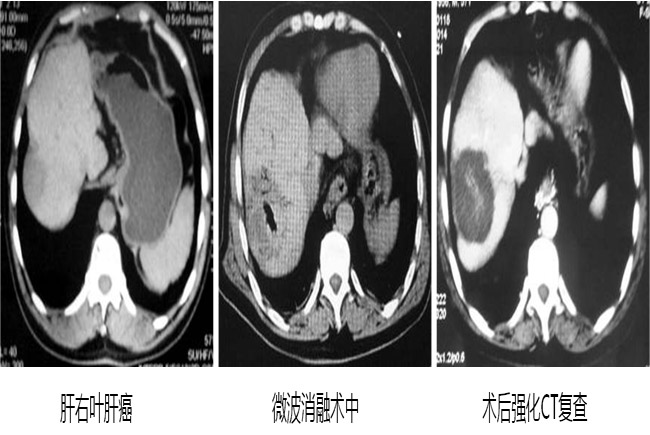

成功案例CT影像对比:

案例一: